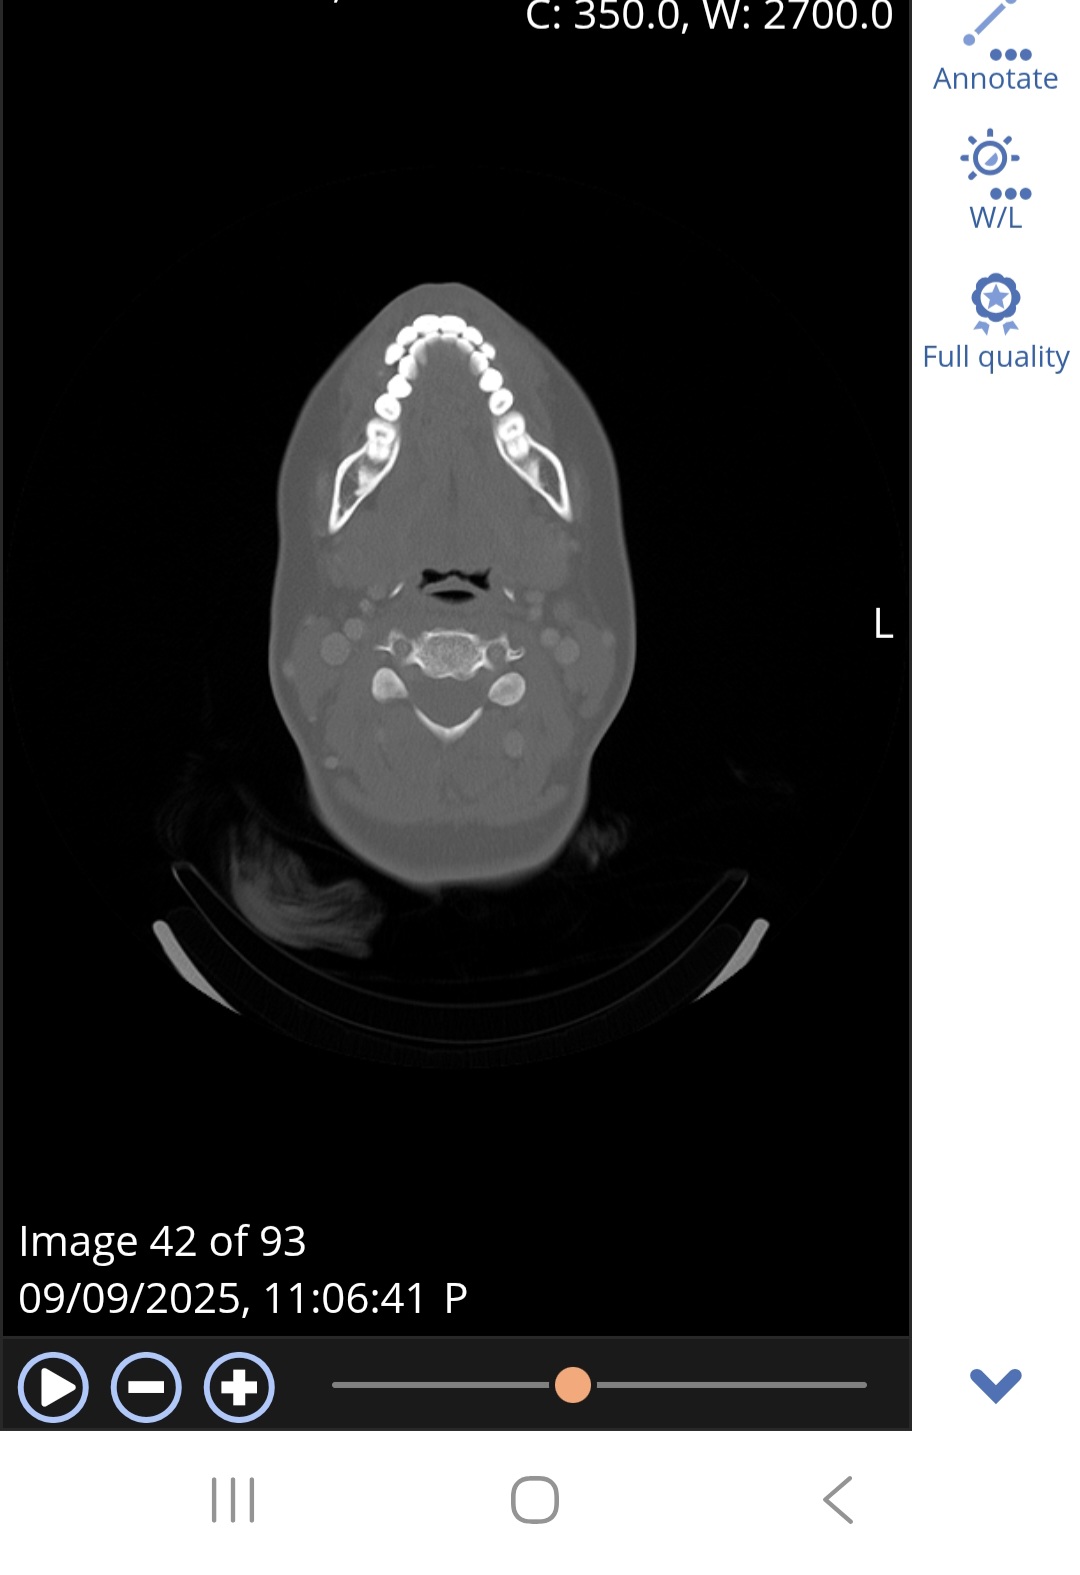

@Happyface12e not quite the right slice. Here’s an image of my C1 to help you know what to look for. Make sure you see the white circle in the top middle of the vertebrae:

Thanks for sharing. Is this what you mean?